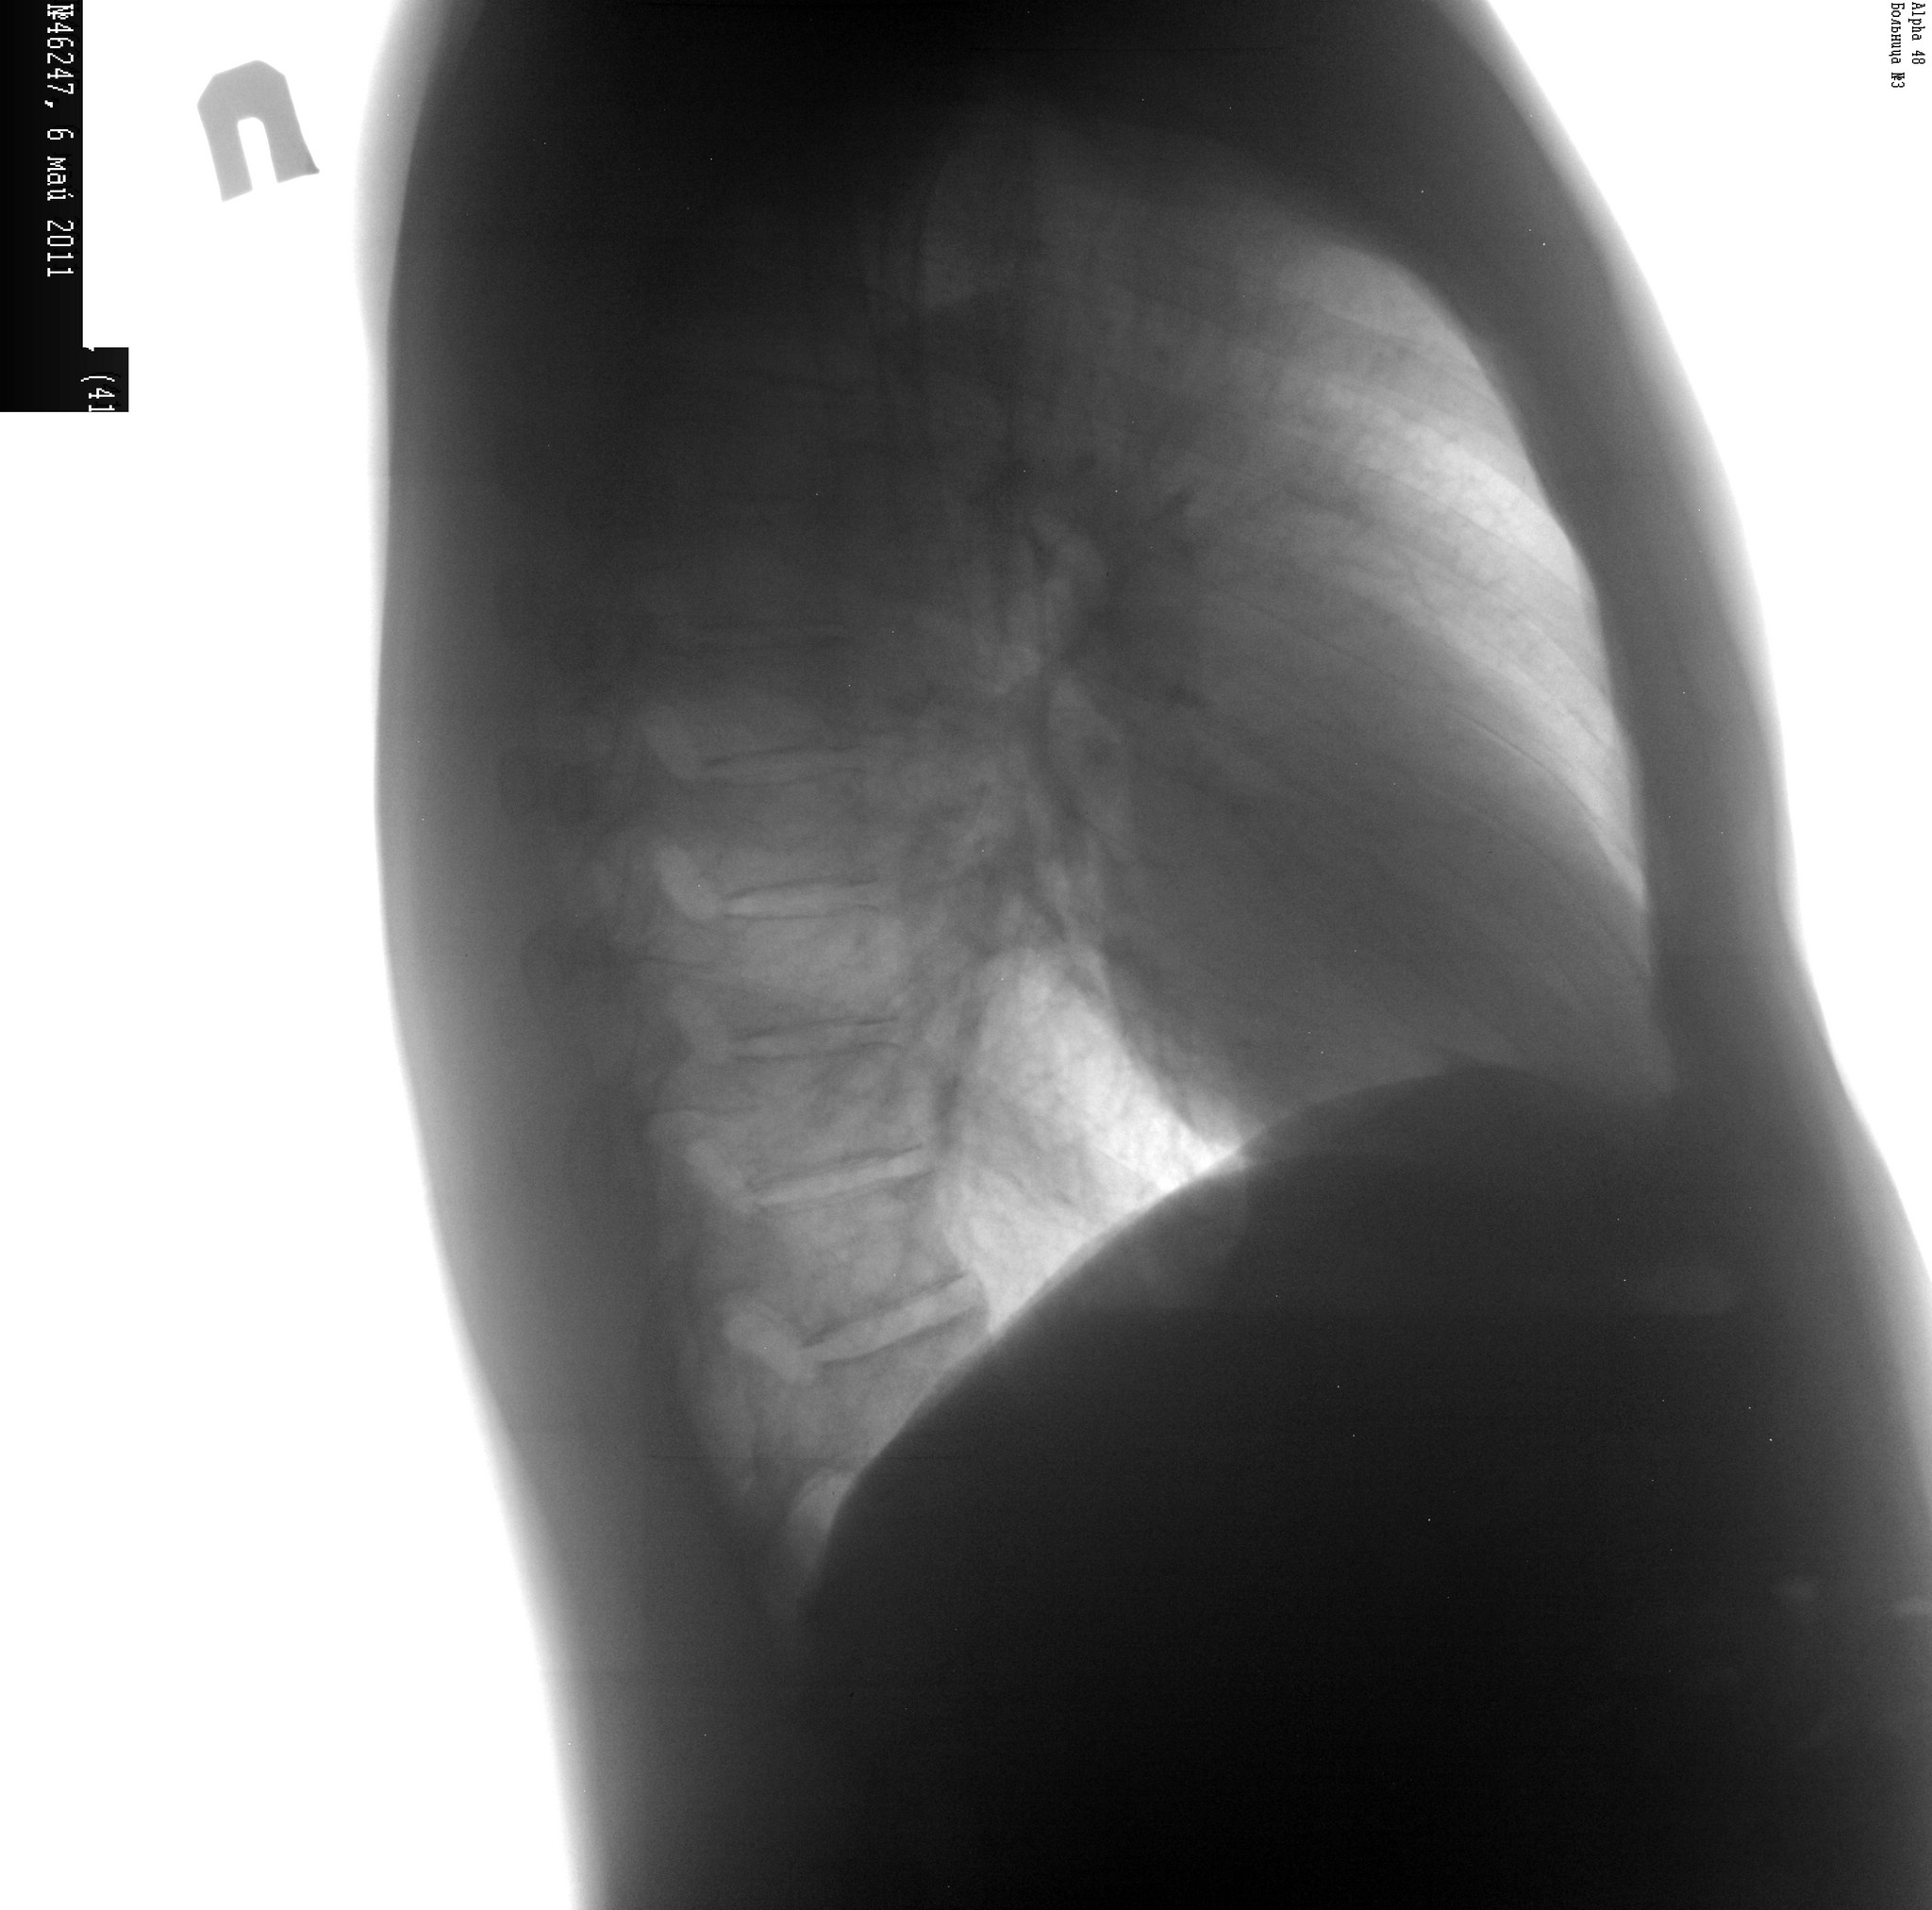

Спасибо)) Написал в заключении дренированная полость? и поствоспалительная плевродиафрагмальная спайка в правом реберно-диафрагмальном синусе. На боку тоже не нашел.

Маленькая полость справа в проекции переднего отрезка 3-го ребра. На боковой я ее не нашла.

По-моему, это вообще "тень на плетень"... Я бы на скопии вдох-выдох сделала. То, что никакого тбс там нет - это точно (работаю в туб дисп - насмотрелась) - каверн на фоне неизмененной легочной ткани не бывает, даже таких мелких. Окружающая легочная ткань абсолютно интактна. Полостюшка, конечно же, рисуется, но большой вопрос, есть ли она. Задние снимки очень помогают, не стоит пренебрегать.